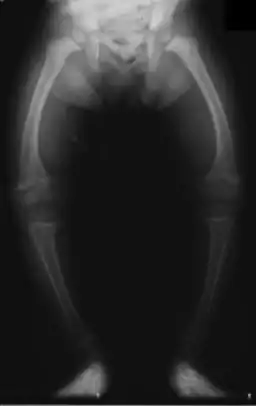

| عکسبرداری از پاهای کودکی ۲ ساله که به راشیتیسم مبتلا است. | |

خمیدگی استخوانها از علایم «کلاسیک» راشیتیسم است که در استخوان پاها و قفسهٔ سینه به وجود میآید. این نقص در جمجمه نیز ممکن است به وجود آید؛ در این صورت جمجمه حالت بیضیشکل خود را از دست میدهد. در صورت وخیم بودن بیماری، خمیدگی در استخوانهای بلند و ستون مهرهها نیز ظاهر میشود. این خمیدگیها با درمان در سنین کوکی معالجه میشوند.